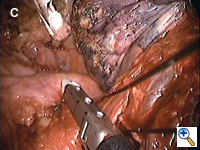

Dissecting around a pulmonary vessel is basically the same as in conventional, open surgery. We use a right-angle Mixter clamp to go around a vessel, and then loop it with a heavy silk ligature. With gentle traction on the suture, a dental pledget is used to gently dissect the undersurface of the vessel. A mechanical stapler (Endo-GIA 30V; Autosuture, United States Surgical, Norwalk, CT) is then introduced through one of the other two ports (depending on the alignment), but usually the camera port (with the thoracoscope repositioned to view through the minithoracotomy wound) to staple-transect the vessel. Appropriate traction (using a sponge holding forceps from the other port) is crucial in aligning the vessel with the stapler for transection (Figure 3). In recent years, we have been using more frequently ligation of pulmonary arterial branches with extracorporeal knots instead of mechanical staplers mainly to reduce cost.[5] We tend not to use many endoclips for small pulmonary branches, as their presence could interfere with the subsequent use and functioning of the endostaplers.

The lobar bronchus is divided with a linear mechanical stapler with a built in blade for transection (Endo-GIA 30 with closed staple height of 1.5 mm; Autosuture, USC, Norwalk, CT). The mainstem bronchus requires use of a different stapler that necessitates manual transection (Roticulator 30 with closed staple height of 2 mm; Autosuture, USC, Norwalk, CT). The integrity of the bronchial stump is then tested to 35 cm of airway pressure in the usual manner underwater.